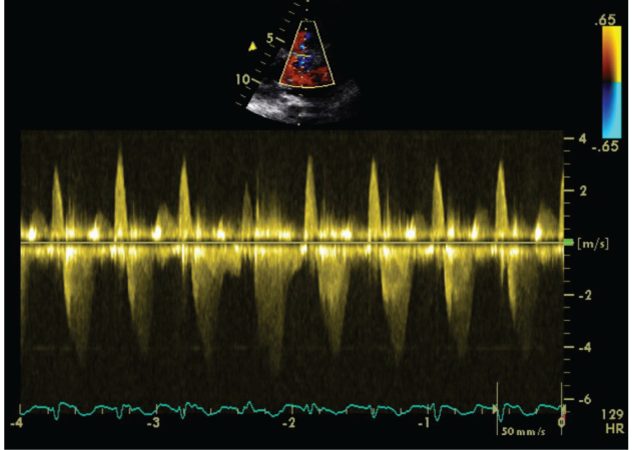

We carried out an Exercise Stress Echocardiogram using a semi-supine bicycle using WHO protocol using a 3-minute step protocol of 20-40 watts at 60-75rpm until volitional fatigue. All basic haemodynamic parameters were recorded at rest and at each stage of exercise (BP, heart rate, Oxygen saturation, electrocardiogram). We assessed his shunt in para-sternal long axis window (PLAX). Consultant cardiologist and senior cardiac physiologist carried out the test. We used colour doppler across interventricular septum to identify the VSD. Once it was identified, we tilted the probe to optimize VSD capture. Sample volume was then placed through VSD to obtain pulsed doppler images at rest (Figure 1). Similar pulsed doppler images were obtained at peak exercise (Figure 2). We did direct shunt volume assessment using velocity time integral (VTI). We averaged all VTIs obtained for five cardiac cycles.

Figure 2 Echocardiographic pulse wave doppler signal at stress.

Averaged VTI at rest for left to right (L-R) shunt was 26.32cm and at stress was 21.6cm. Similarly VTI at rest for right to left shunt (R-L) was 78.08cm and at stress was 79.44cm.

Absolute change of VTI ratio during exercise was equal to 0.71 (3.67-2.96). This means that during exercise, right to left shunt was increasing in volume and left to right shunt was proportionately decreasing.